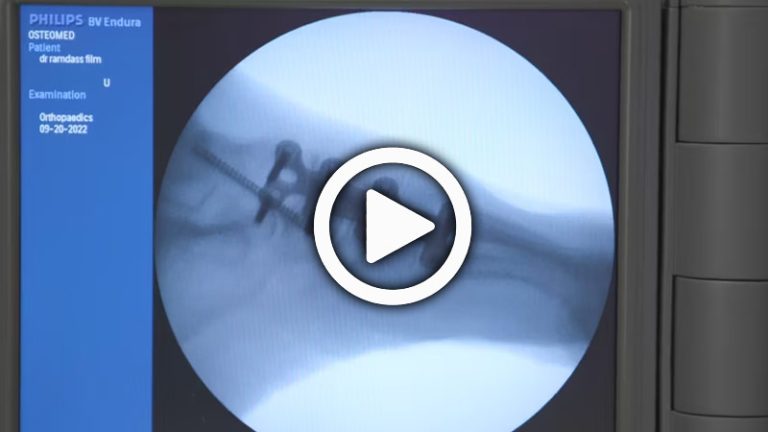

Evans Osteotomy for Adult Acquired Transverse Plane Predominant Flatfoot Deformity with Roland Ramdass, DPM, FACFAS

Using both the ExtremiLock Foot Plating System and PrimaGraft Evans/Cotton Wedges, Dr. Ramdass demonstrates the Evan Osteotomy Surgical Technique for Adult Acquired Transverse Plane Predominant Flatfoot Deformity.